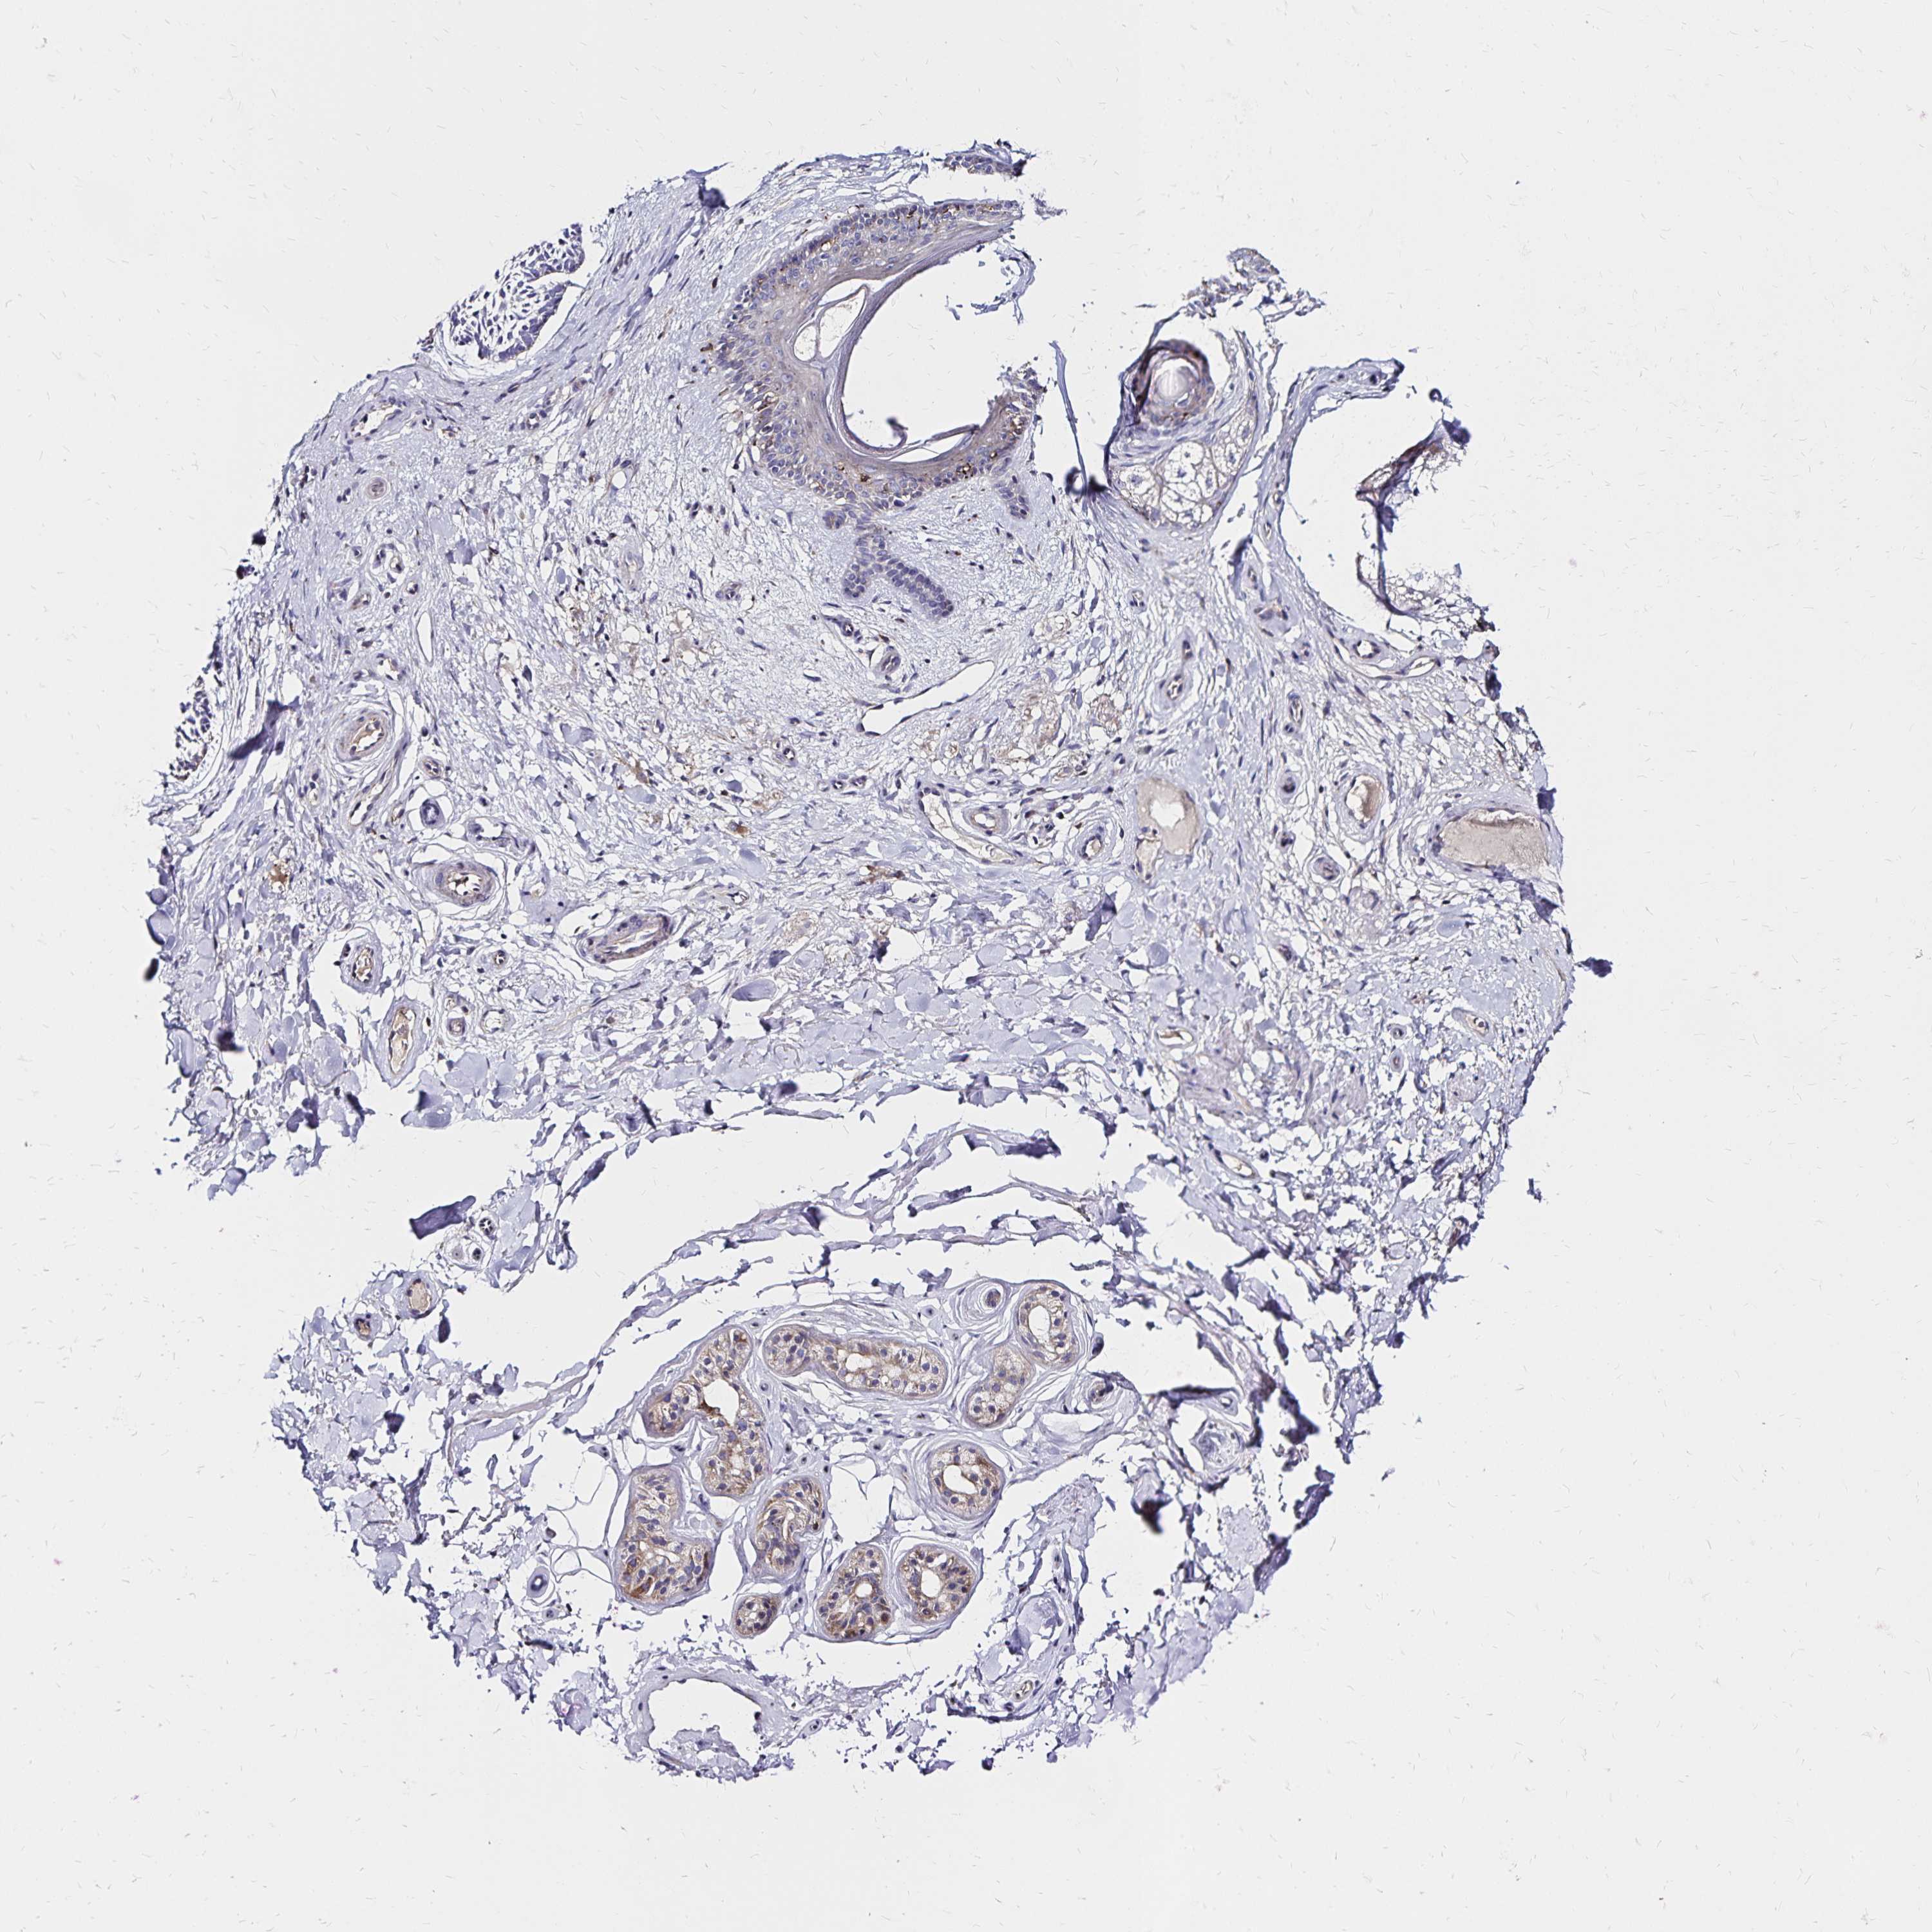

CANCER SKIN CANCER Show tissue menu

Basal cell and squamous cell cancer

SKIN CANCER - Protein expressioni

A mouse-over function shows sample information and annotation data. Click on an image to view it in a full screen mode. Samples can be filtered based on level of antibody staining by selecting one or several of the following categories: high, medium, low and not detected. The assay and annotation is described here.

Each image is clickable and will lead to virtual microscopy that enables deeper exploration of all samples and also displays staining intensity scores, fraction scores and subcellular localization as well as patient and tissue information for each sample.

Antibody HPA064055

Staining

High

Medium

Low

Not detected

Intensity

Strong

Moderate

Weak

Negative

Quantity

>75%

75%-25%

<25%

None

Location

Nuclear

Cytoplasmic/membranous

Cytoplasmic/membranous,nuclear

Basal cell carcinoma

Squamous cell carcinoma, NOS